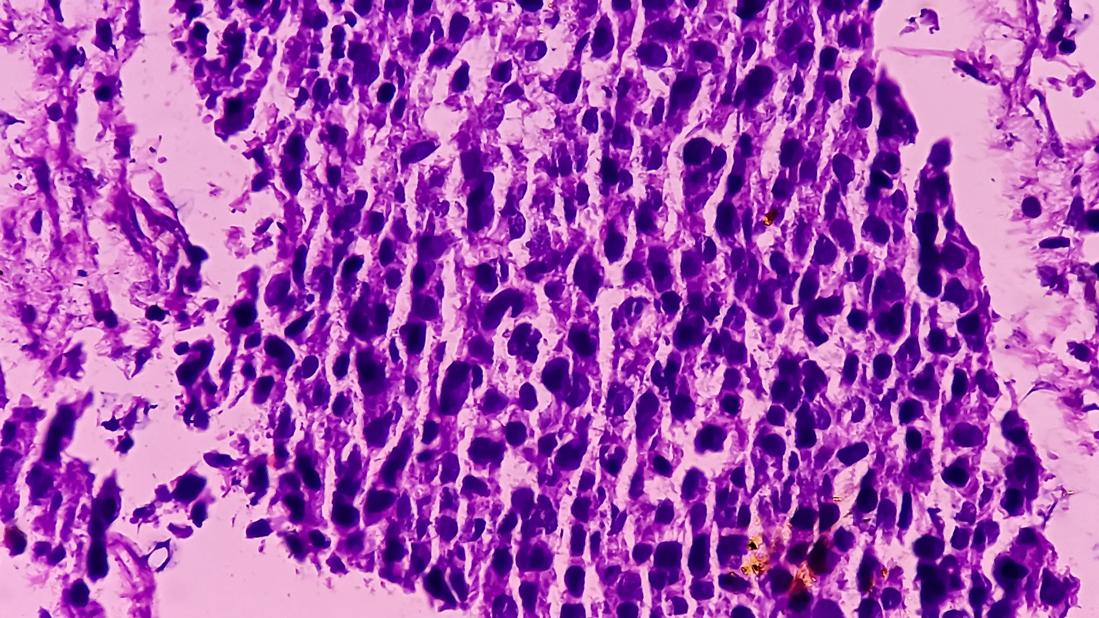

Microscopic view of bladder cancer with variant histology